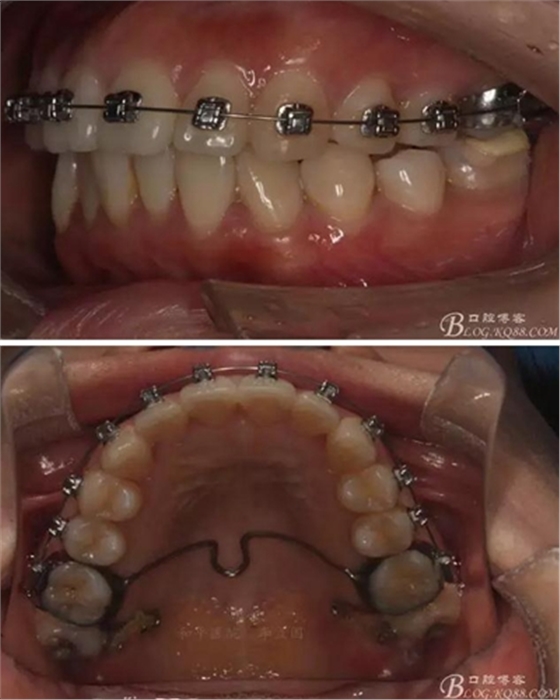

該病例主要為17、27頰側(cè)位同時伴有伸長,當然種植支抗可以解決,但還有簡單實用的辦法嗎?如圖,在橫腭桿遠中延伸出牽引鉤,位置盡量遠離合平面,7粘舌側(cè)扣,牽引力的方向為壓低及舌向,下圖為兩個月的效果,17已到位,27還未到位。